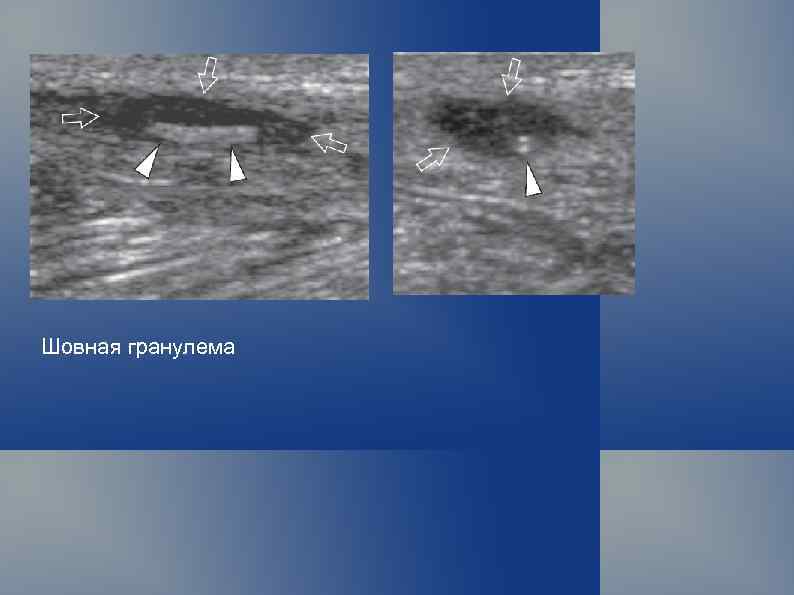

Шовная гранулема

Шовная гранулема